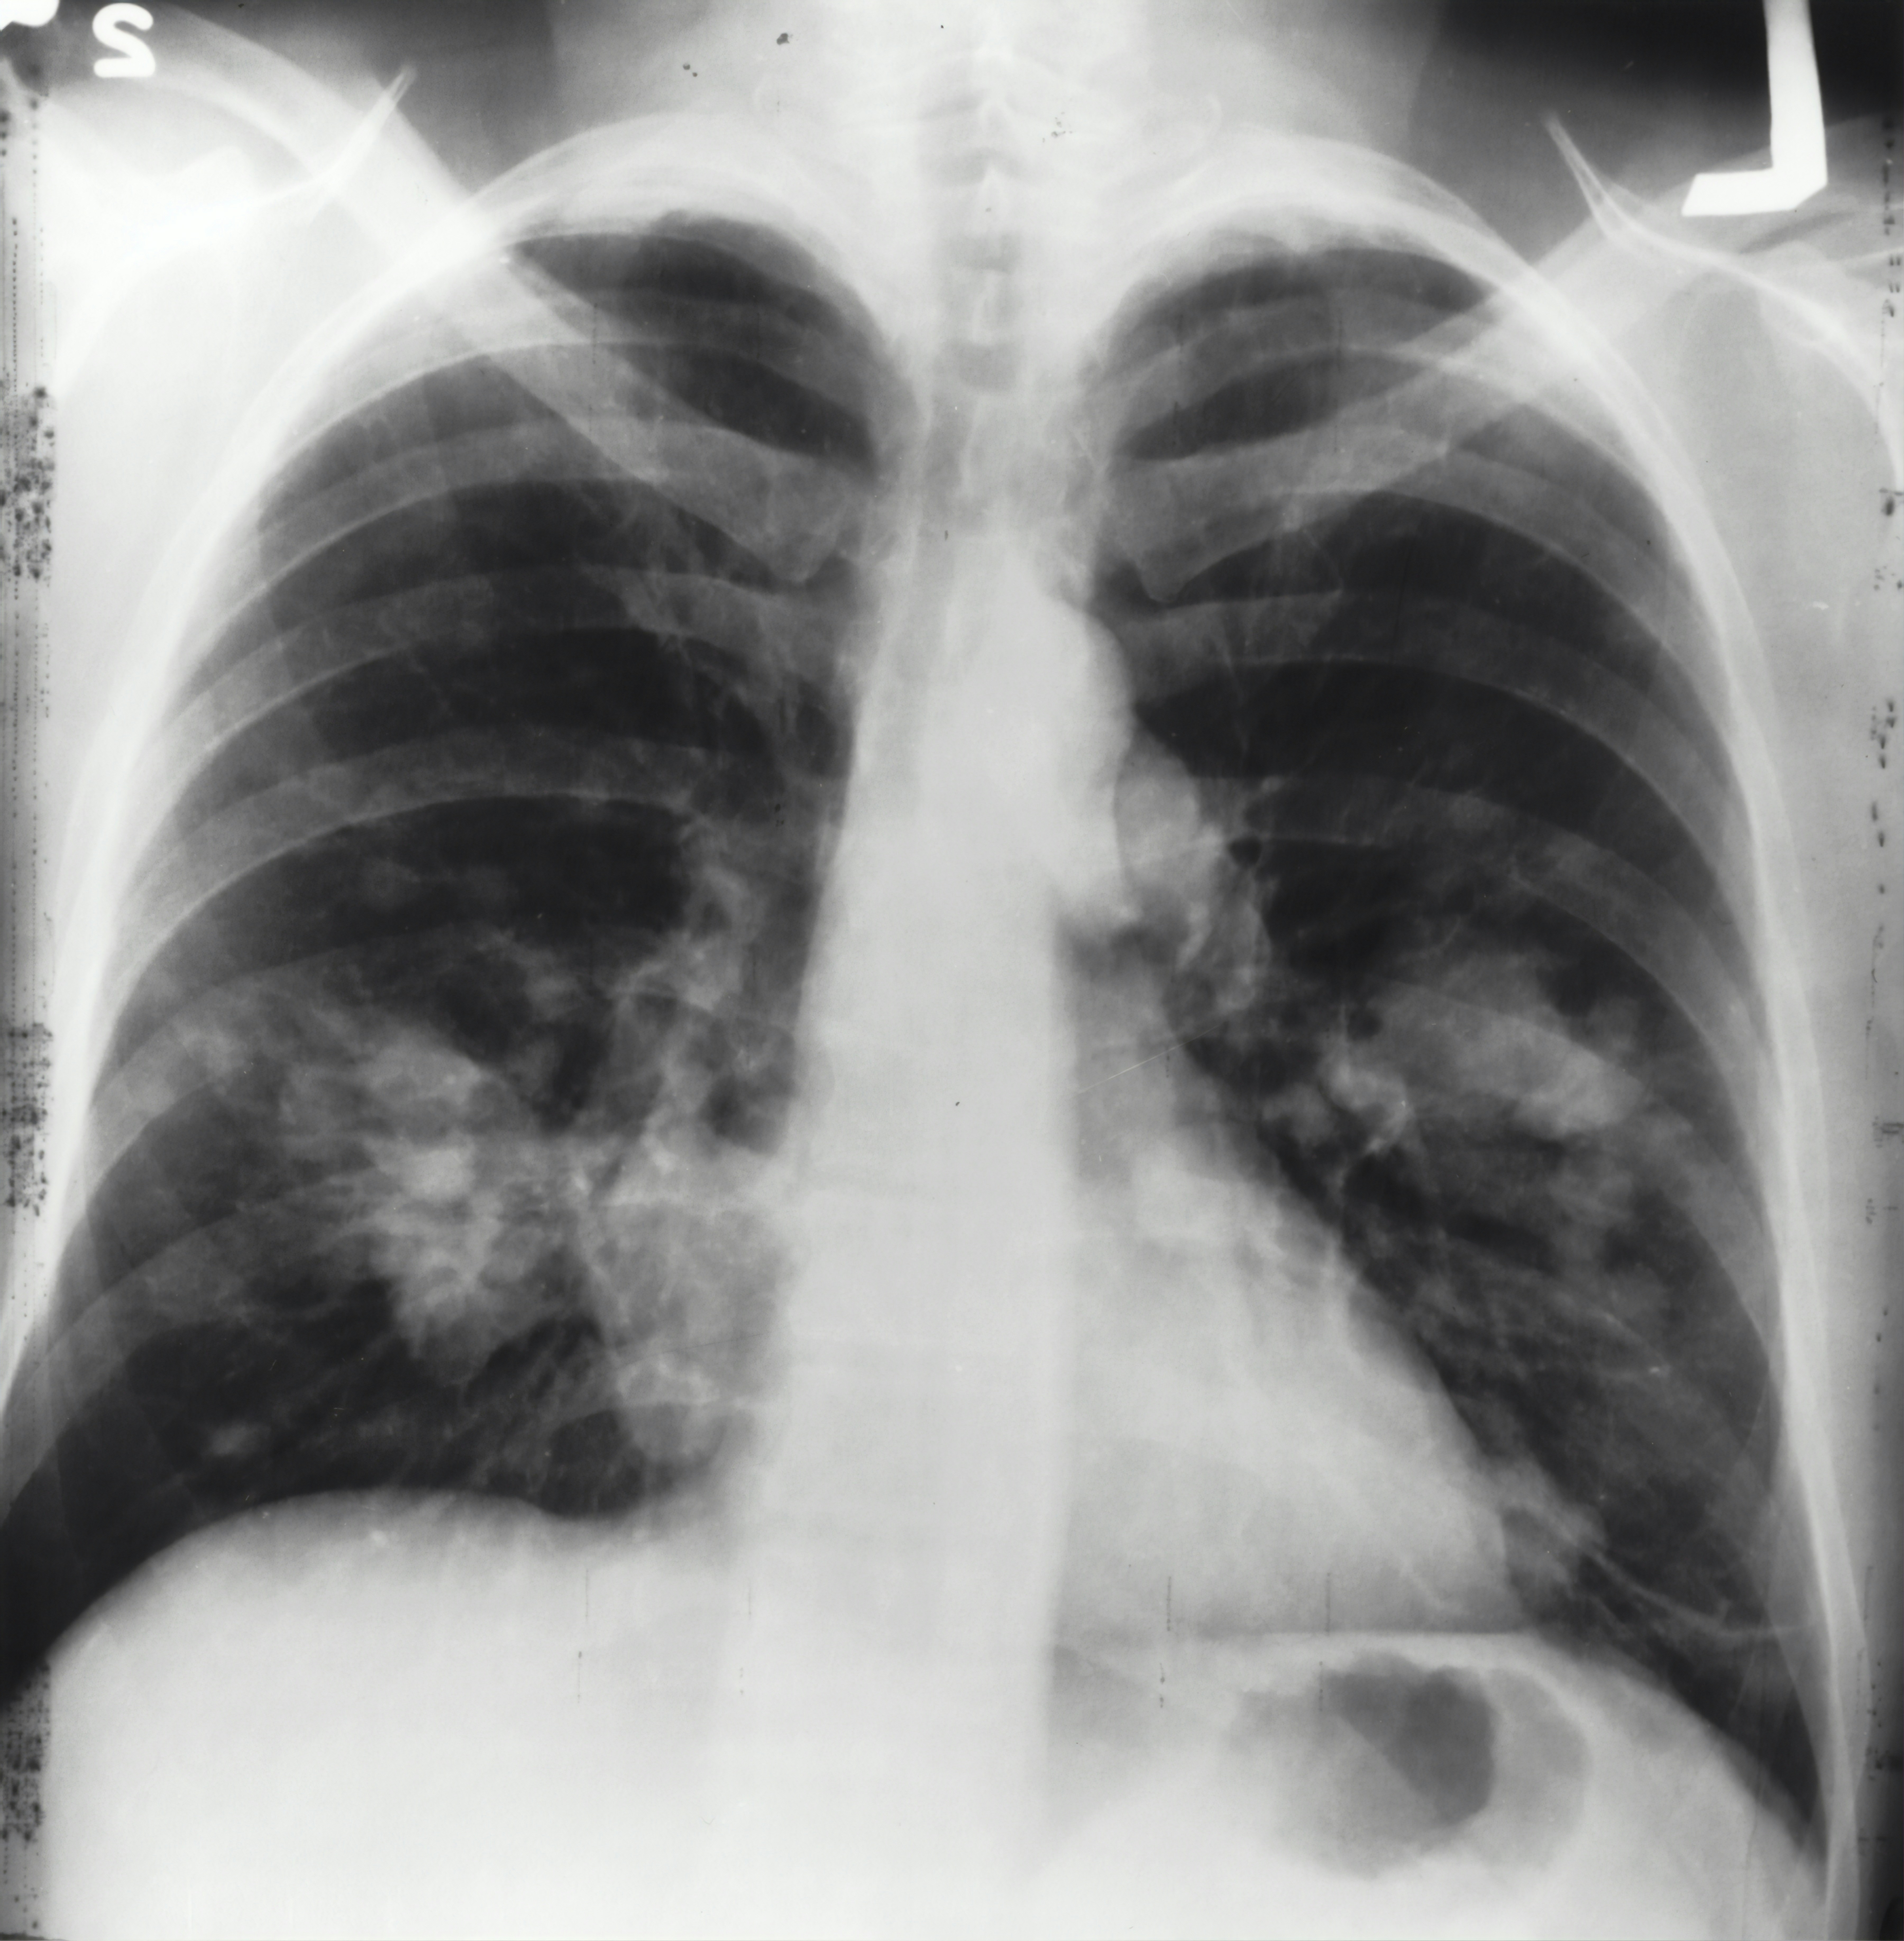

폐에 물이 찼는지 확인하려면 영상검사와 물리적인 청진이 가장 중요합니다. 제가 처음 병원에 갔을 때도 의사 선생님께서 청진기로 폐음을 듣고, 바로 흉부 X-ray를 찍었습니다. 그 결과 한쪽 폐에 꽤 많은 양의 물이 고여 있었죠.

X-ray는 기본이며, 정밀 진단을 위해 CT(컴퓨터 단층촬영)나 초음파 검사를 함께 시행하는 경우가 많습니다. 특히 초음파는 물의 위치와 양, 움직임 등을 실시간으로 확인할 수 있어 진단에 매우 유용합니다.